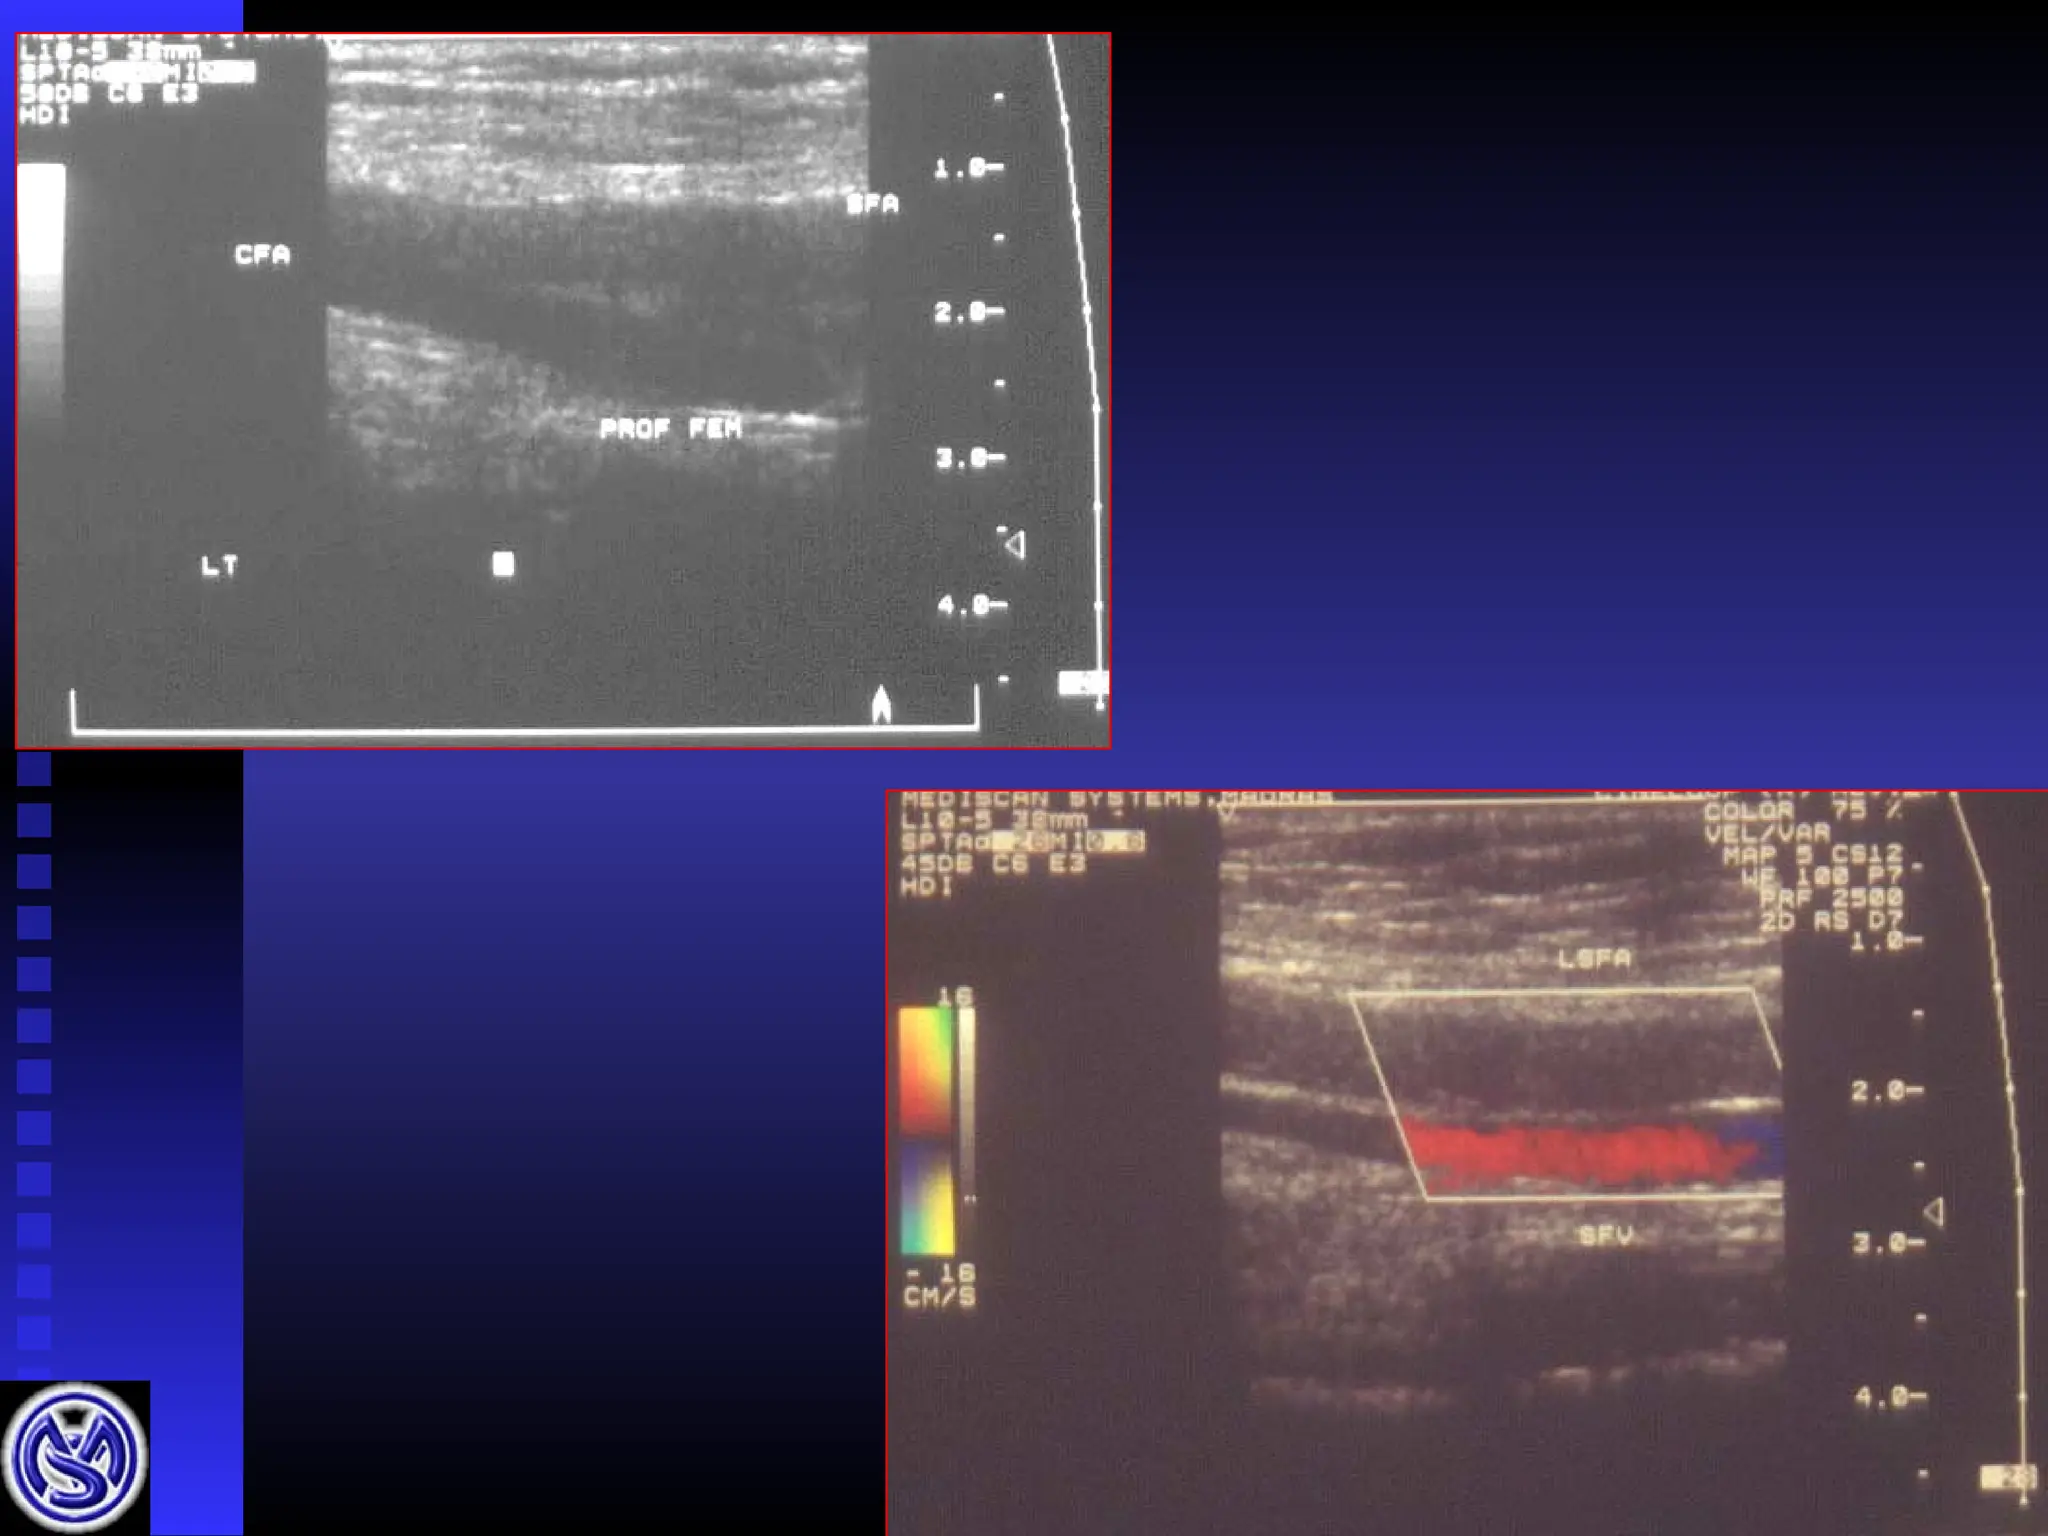

 Image from abdominal aorta to distal vessels

Image from abdominal aorta to distal vessels



Aortic bifurcation

Common iliacs

External iliacs

(internal il.)

Common femoral

Profunda

Superficial femoral A

Popliteal A

Ant tib. / post tib / peroneal A